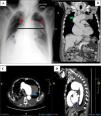

Syphilitic Aortitis: A Mimicker of Mediastinal Mass